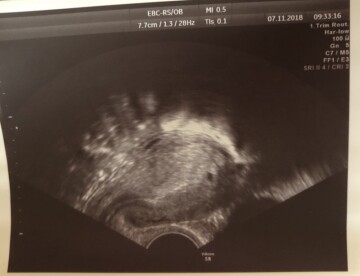

Dobrý den, paní doktorko, ve středu 7.11. Jsem byla na utz a to jsem byla něco 4+tt a šel vidět malý váček viz příloha. V úterý 13.11. Jsem šla na kontorli kvůli výtoku, který je ok. A pan dr tam nebyl tak mě dali k jiné paní dr a ta byle velice nepříjemná a vše trvalo asi 2min... chtělo se mi čůrat a vag.utz řekla že vidí jen dutinku a nazdar.. vzali mi krev které vycházelo 1877 ml.. poslední ms jsem měla 6.10.2018... strašně mě vYděsila mimoděložním(což nechápu, v děloze už šlo vidět) a pak mi řekla “budu brát teda, že jate těhotná” nechápala jsem. Nemůžu spát. Protože jsem po potratu a nerada bych to prožívala znova. Beru ráno gynprodyl a vitamíny femibion. Děkuji za váš názor

Dobrý den, pokud byste byla těhotná více než 5 týdnů, měl by na Uz být vidět již gestační váček alespon s náznakem plodu a po 6 týdnech již srdeční akce. Jedna hodnota hCG sama o sobě nic o diagnoze neřekne. hodnoty jsou potřeba alepon dvě, aby se dalo porovnat, zda hCG adekvátně roste, či je stejné nebo klesá. Co se týče mimoděložního těhotenství, pak tzv. pseudogestační váček (dutinka) může být na UZ patrna i u něj...určitě se tedy nedá na základě vašich informací říci, zda se jedná o mimo děložní těhotenství či nevyvíjející se těhotenství v děloze, ale doporučovala bych za několik dní kontrolu. Pokud se jedná o těhotenství, které se vyvíjí dobře, pak by na Uz měl být za pár dní vidět plod.